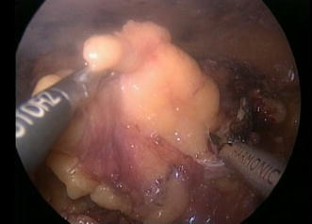

Laparoscopic partial nephrectomy without intracorporeal suturing

Partial nephrectomy has gained wider acceptance as a surgical technique in treating small renal tumors. Laparoscopic partial nephrectomy (LPN) still remains a technically demanding surgery to this day. We present our technique of laparoscopic partial nephrectomy, one that is performed without intracorporeal suturing.

We performed LPN on 31 patients with localized renal parenchymal tumor (stage T1). The procedures were done from September 2009 to March 2015 at the Kaohsiung Medical University Hospital and the Kaohsiung Municipal Ta-Tung Hospital. Our technique involves the covering of renal defect layer by layer with FloSeal, Tisseel and a fat pad after monopolar coagulation.

Fig. 1